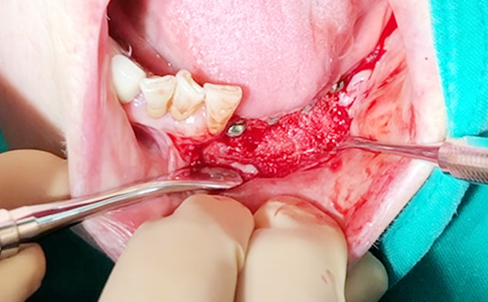

Implants/Bone Grafting

Simultaneous bone graft and implant placement